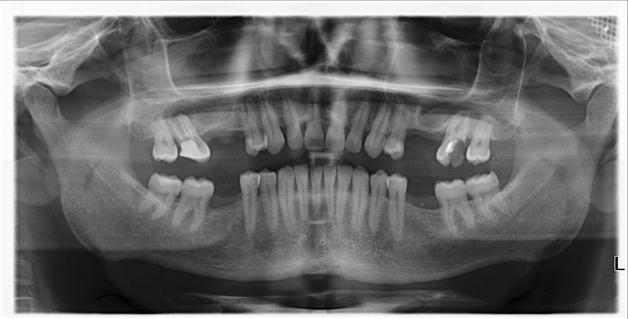

Зубная имплантация — это процесс восстановления зубов, удаленных вместе с корнем. В костную ткань вживляется имплантат (или имплант, имплантант, это одно и то же), который служит заменой корню зубу. Сверху на нем фиксируется искусственная коронка — видимая часть зуба. Таким образом удается полностью имитировать живой зуб.

Перед имплантацией зубов обязательно сдаются анализы крови и мочи. Врачу необходимо знать состояние вашего организма и понимать, с чем придется столкнуться во время проведения операции, может ли возникнуть риск отторжения имплантатов. Среди анализов — общий крови и мочи, на глюкозу, свертываемость крови, инфекционные и онкологические заболевания. Уточняются также группа крови и резус-фактор. Женщинам дополнительно необходимо сдать анализы на уровень гормонов в организме.